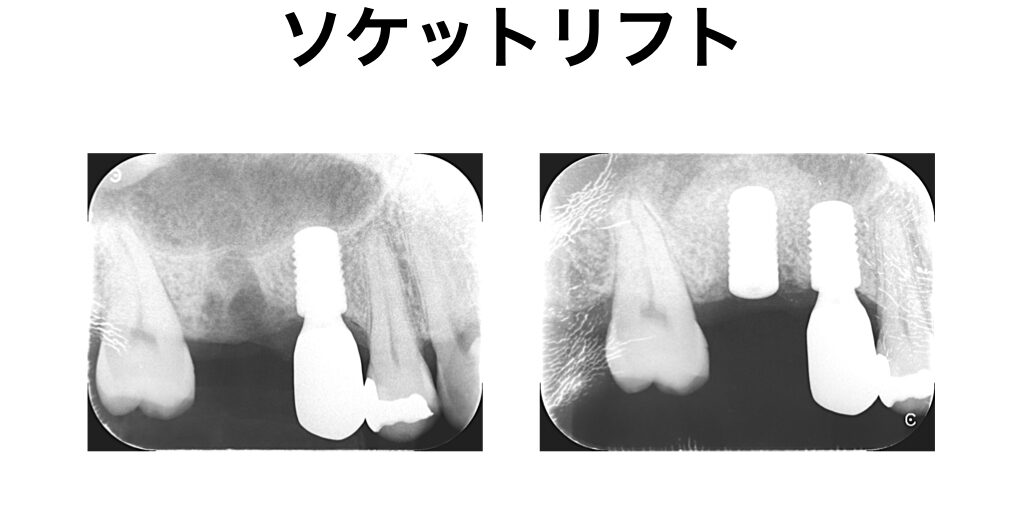

ソケットリフト

ソケットリフトは上顎に骨が足りない時に行う骨造成です。

上顎には上顎洞といい、鼻と交通している空洞があります。さらに抜歯すると骨が痩せやすく、インプラントを埋入する骨の厚みが足りなくなるケースがあります。ソケットリフトは上顎洞内に骨を作るテクニックのひとつです。インプラントの手術と同時に、埋入する穴から骨を作るので傷が小さいことが特徴です。